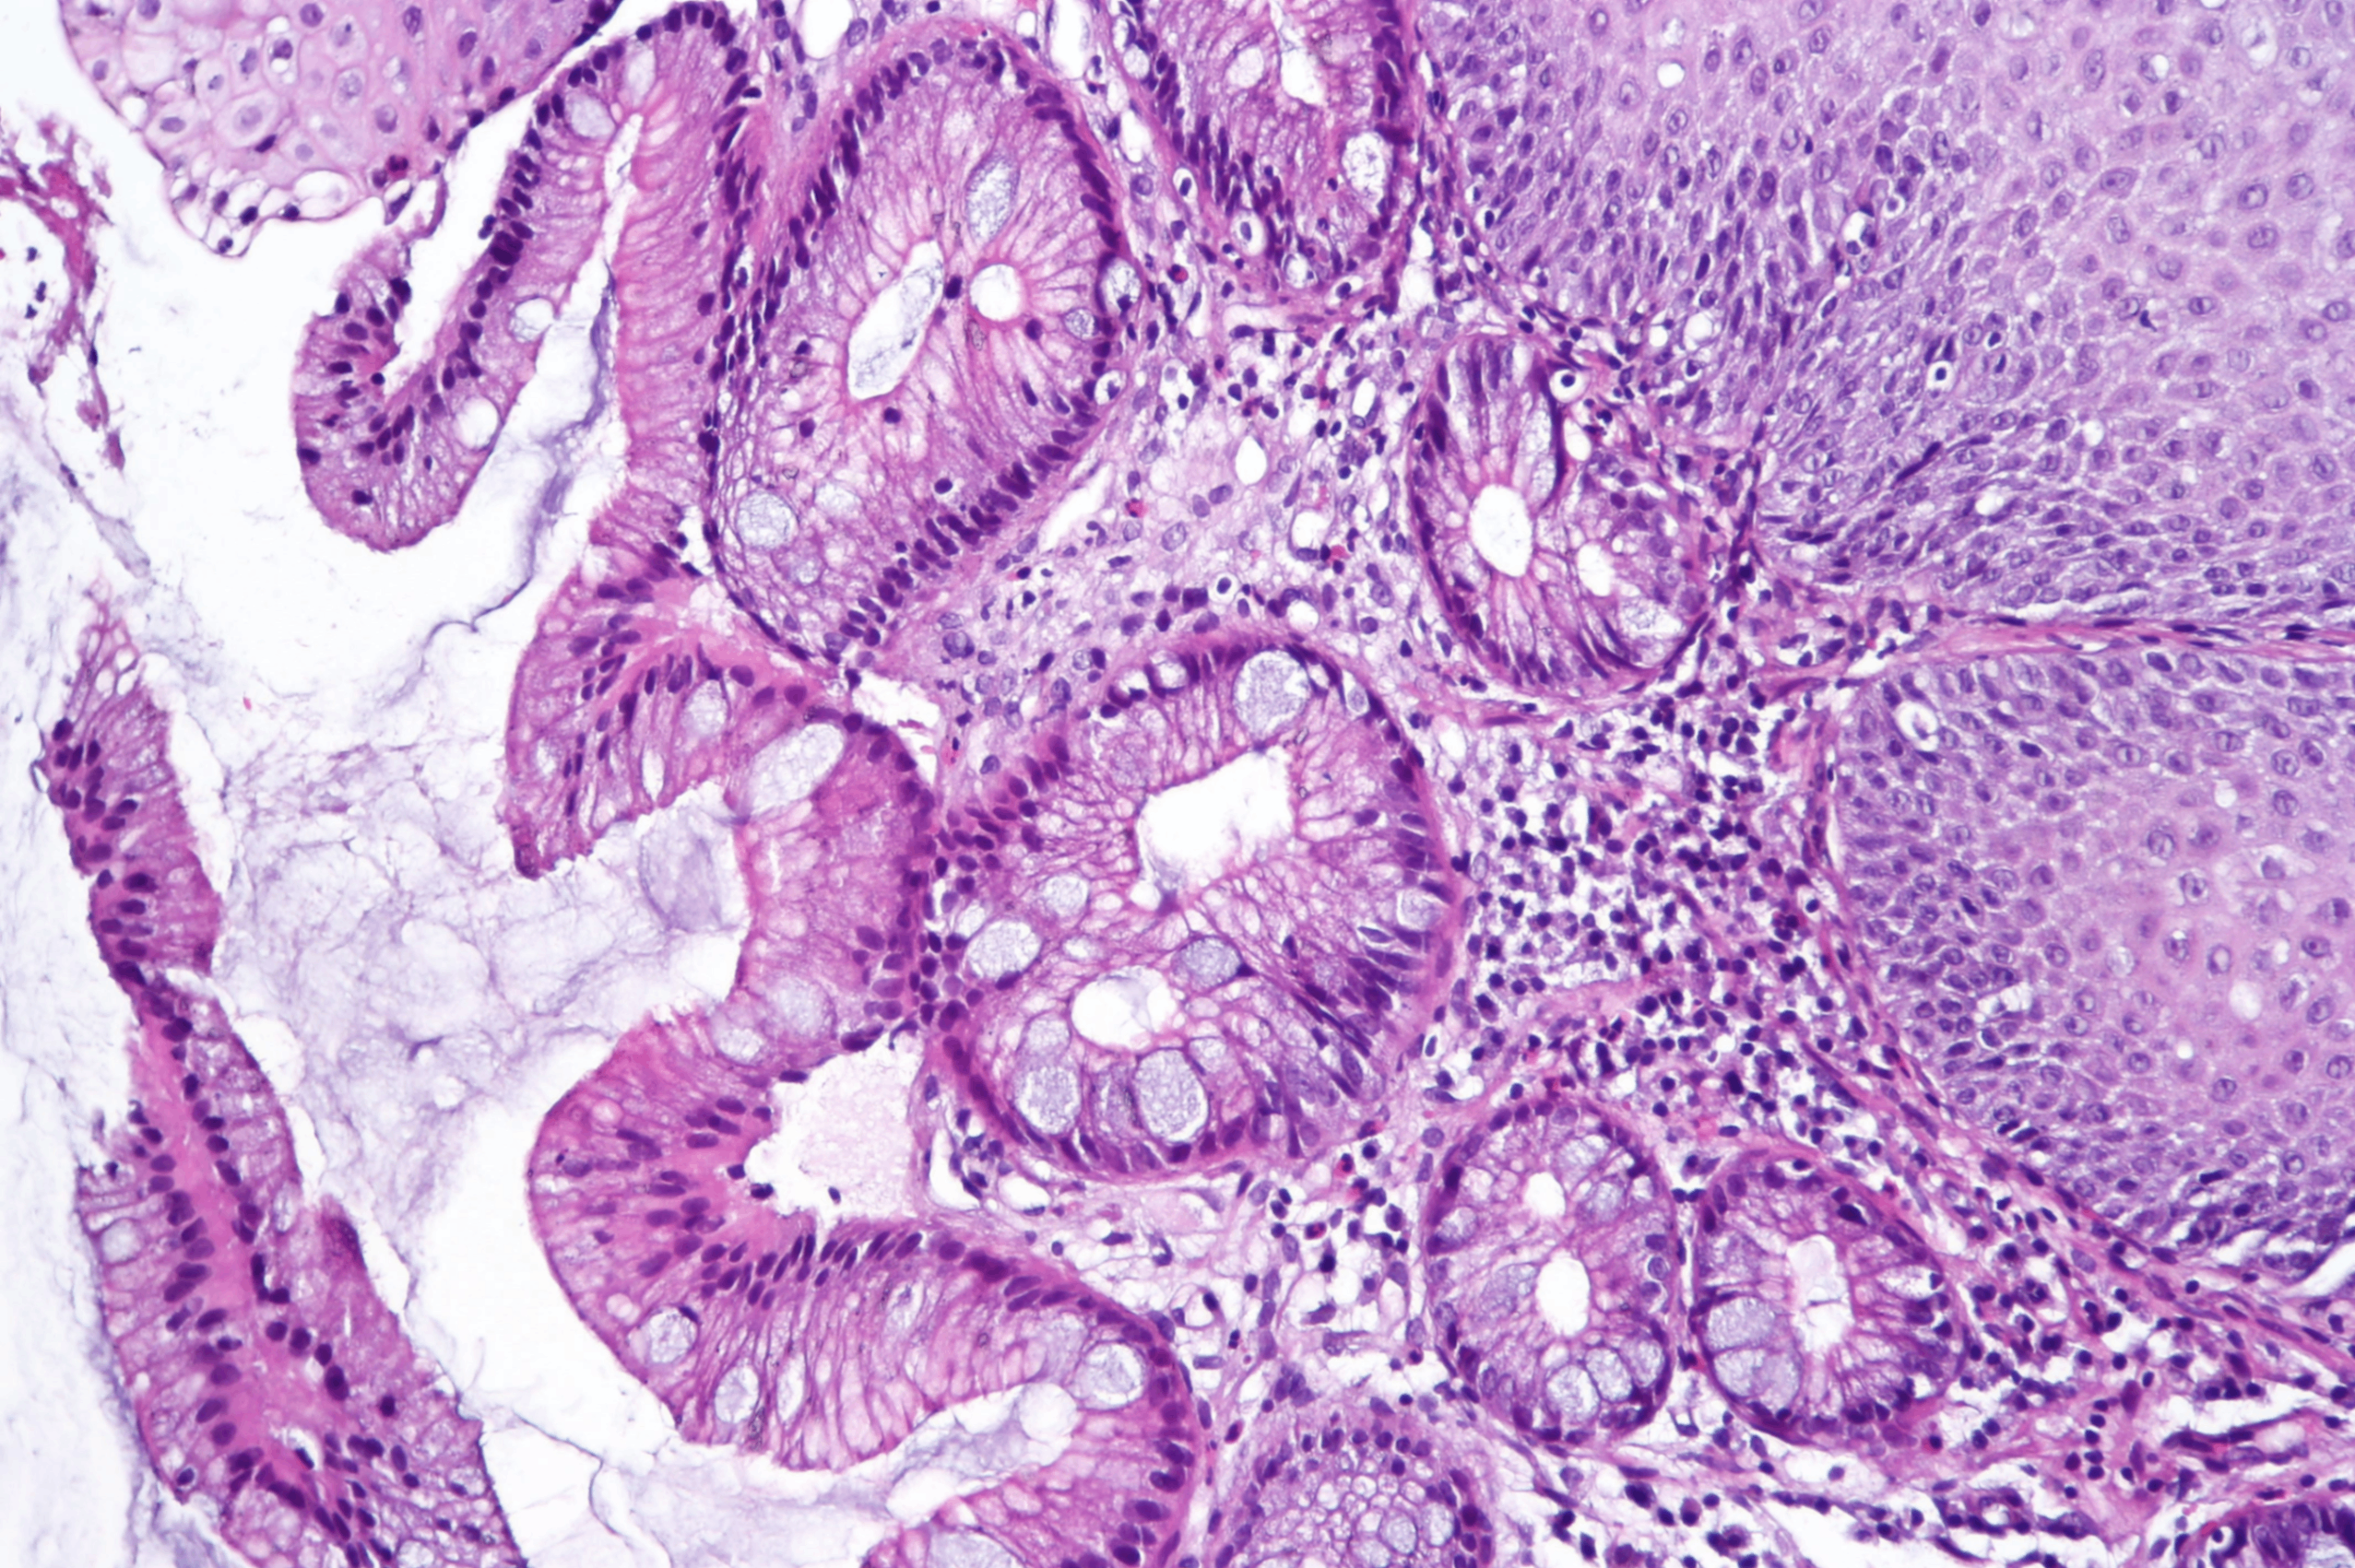

3) 조직학적 소견

• 편평상피가 장형 원주상피로 대체

Goblet cell 존재 → 진단에 필수적

- 창백한 청색의 mucuous vacuole로 확인 가능

• 진행 시 이형성(dysplasia)도 관찰 가능

- 샘 조직의 irregular shape, cell crowding

- nuclear-to-cytoplasm ratio의 증가, 미성숙한 상피 세포

→ Lamina propria 침범 시 intramucosal carcinoma로 진단

Barrett esophagus, Wikimedia Commons